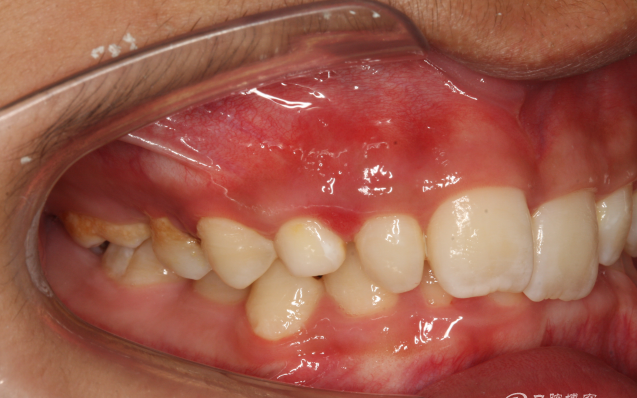

圖2.右側(cè)位咬合影像:乳尖牙滯留